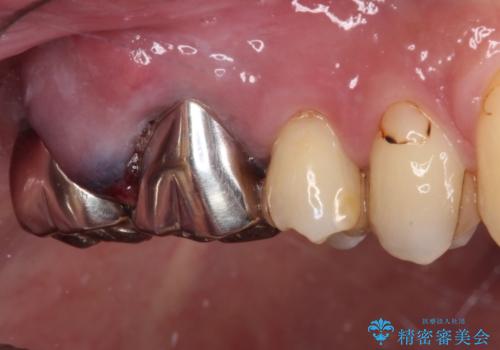

- 目立つ銀歯と欠けて痛みを感じる歯を気にして来院された患者様です。

手前の歯は神経の炎症がとても強く、保存不可能であったため、根管治療を行うこととしました。

目立つ銀歯も根管治療を行い、その後2本の歯をオールセラミッククラウンにて補綴治療を行うこととしました。